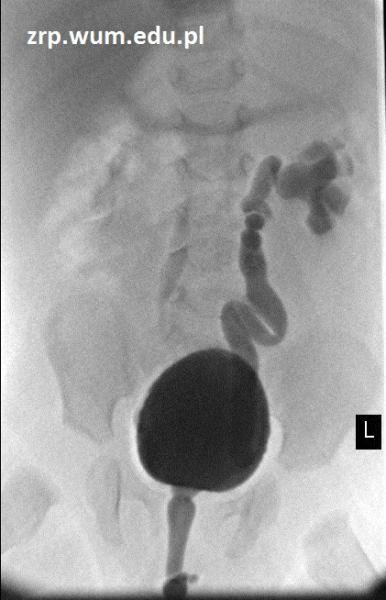

Rozpoznanie: W wykonanym badaniu cystografii mikcyjnej - pęcherz moczowy o zarysach gładkich. Cewka moczowa prawidłowa. Uwidoczniono obustronne odpływy czynne - po stronie prawej II stopień, po lewej III/IV stopień.